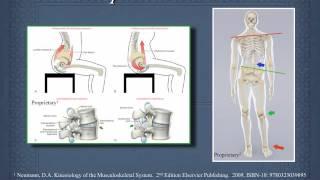

The Common Mechanisms Behind Back Pain: Kinetic Chain

Mark Brezinski MD,PhD,CPT

608

2,027

8 лет назад

Common Mechanisms of Knee Pain: Kinetic Chain and Nervous System

Mark Brezinski MD,PhD,CPT

377

1,258

8 лет назад